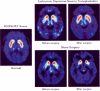

Transplantation of human fetal dopamine neurons into the brain of Parkinson's disease patients started in the late 1980s, less than 10 years after experiments in rats showed that embryonic dopamine neurons from a narrow window of development are suitable for transplantation. For human transplantation, the critical stage of development is 6 to 8 weeks after conception. Because putamen is the basal ganglia structure most depleted of dopamine in Parkinson's disease and because it is the structure most closely mapped to the motor cortex, it has been the primary target for neurotransplantation. The double blind trial conducted at the University of Colorado, Columbia University, and North Shore University is the first controlled surgical trial performed in the field of neurosurgery. Results have shown that transplants of fetal dopamine neurons can survive transplantation without immunosuppression and without regard to the age of the patients. Transplants improved objective signs of Parkinson's disease to the best effects of L-DOPA seen preoperatively. Placebo surgery produced no clinical changes. In subjects in whom transplants replaced the need for L-DOPA, the implants replicated the preoperative effects of L-DOPA, including dyskinesias in susceptible patients. Our trial has provided the first controlled evidence that dopamine cell transplants can improve the clinical state of patients with Parkinson's disease.